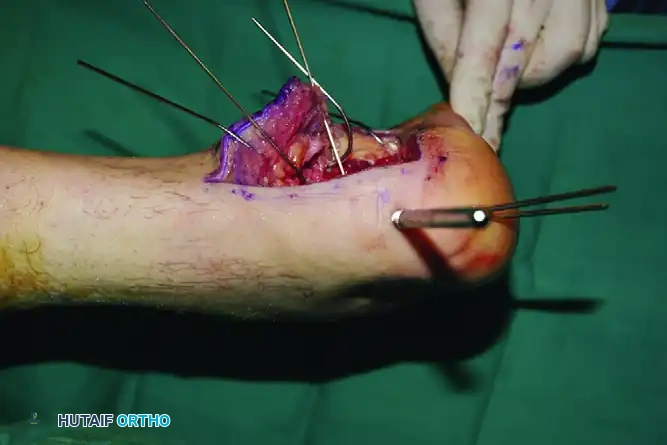

Elevate the entire flap en bloc. To maintain exposure without causing crush injury to the flap edges (which occurs with self-retaining retractors), utilize the "no-touch" Kirschner wire (K-wire) retraction technique.

- Place stout K-wires (1.6 mm or 2.0 mm) longitudinally into the fibula, the lateral aspect of the talus neck, and the cuboid.

- Bend these wires backward to act as a scaffold, gently holding the full-thickness flap out of the surgical field. Once secured, the flap does not need to be touched again for the remainder of the procedure, drastically reducing the risk of marginal necrosis.

Step 3: Tuberosity Disimpaction and Alignment

The tuberosity is typically displaced superiorly, anteriorly, and into varus. Reduction is achieved indirectly.

- Insert a large, threaded Steinmann pin (or a 5.0 mm Schanz pin) transversely into the posteroinferior aspect of the tuberosity fragment, driving it from lateral to medial.

- Use this pin as a "joystick" to manipulate the tuberosity. Apply axial traction to restore length, plantarflex the fragment to restore height (Böhler’s angle), and translate it laterally to correct the varus deformity.

- Once the tuberosity is reduced to the constant sustentacular fragment, secure it with provisional fixation using axially directed K-wires introduced from the non-weight-bearing portion of the heel directly into the sustentacular fragment.